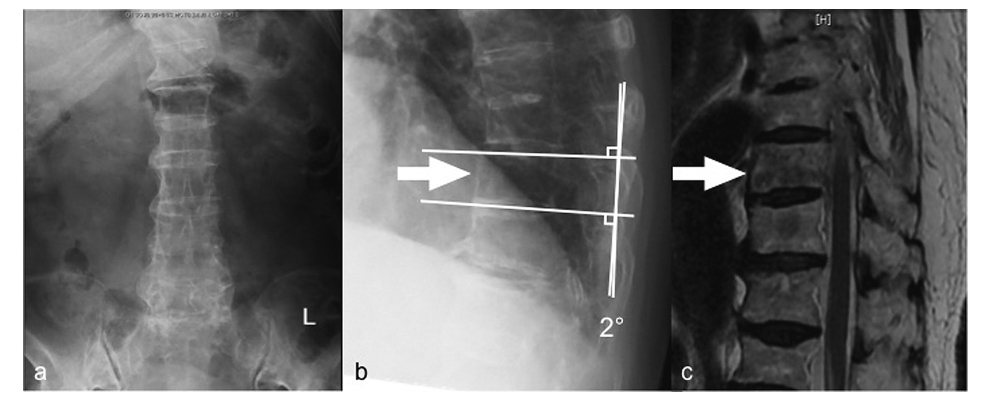

An 86-year-old woman with no significant past medical history presented with acute back pain after a fall and was transferred to her local hospital. Plain radiographs showed a bone bridge spanning more than four intervertebral bodies without a narrow intervertebral space (Figure 1a, b). Magnetic resonance imaging (MRI) showed a Th10 fracture (Figure 1c). She was diagnosed as having DISH and a Th10 fracture. She underwent conservative treatment because of her extreme age and no clear instability. She started gait exercise at 2 weeks after injury with immobilization by a rigid orthosis. Twenty-five days after injury, she presented with bilateral leg paralysis and numbness. Since delayed paraplegia was suspected, she was transferred to our hospital for surgical treatment. On admission, she had bilateral leg paralysis (grade 3 on manual muscle testing: MMT) below the iliopsoas and hypoesthesia of the anterior thighs. She had no bladder or bowel dysfunction. A lateral plain radiograph showed a decreased local kyphotic angle (Figure 2a). Computed tomography (CT) showed anterior expansion with a bone defect in the Th10 vertebral body and subsequent decreased kyphosis due to distraction-extension injury (reverse Chance fracture) (Figure 2b) and ossification of the ligamentum flavum at bilateral T10/11. MRI showed an intramedullary high-intensity area on T2-weighted images (Figure 2c), indicating instability and non-union at the same level. She underwent surgery 50 days after the injury. Laminectomy of Th10, partial laminotomy of Th11, Th7-L1 posterior fusion with pedicle screws and additional stabilization with laminar hooks to Th6 and L1 laminae to avoid back out of the screws, Th9-11 anterior fusion with a plate, and autologous bone grafting were performed simultaneously (Figure 3). In situ fusion in the prone position was done with no alignment correction. After surgery, her paralysis improved, and she started gait exercise with no limitation. Eight days after surgery, she presented with low back pain and paralysis (grade 2 on MMT) in her legs with no apparent cause. CT revealed an L1 fracture in the middle of the vertebral body, which was the caudal end of the fusion (Figure 4b). The patient refused further surgical treatment and werewas transferred back to the previousinitial hospital. She was bedridden thereafter because of the pain, and theher paralysis did not improve. Finally, shethe patient was die of pneumonia 4 month after surgery.

Plain radiographs at the initial visit to the local hospital showing a bone bridge spanning more than four intervertebral bodies. (a, anteroposterior view; b, lateral view). T1-weighted MRI showing a Th10 vertebral fracture (c).